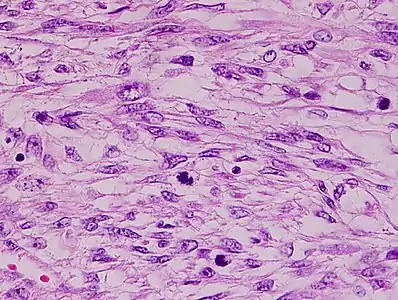

The tumors are usually hemorrhagic and soft and microscopically marked by pleomorphism, abundant (15–30 per 10 high-power fields) abnormal mitotic figures, and coagulative tumor cell necrosis. The differential diagnosis, which includes spindle cell carcinoma, spindle cell melanoma, fibrosarcoma, malignant peripheral nerve sheath tumor and even biphenotypic sinonasal sarcoma, is wide.

Histopathology of leiomyosarcoma shows variable atypia, often with cytoplasmic vacuoles at both ends of nuclei, and frequent mitoses.[11]